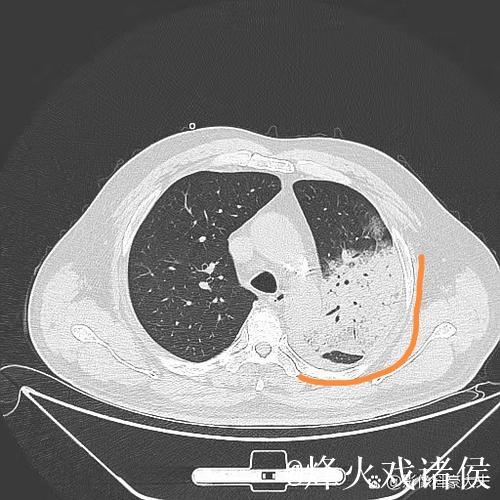

肺炎之所以让人恐惧,不仅因为它可能引发呼吸衰竭,甚至威胁生命,更因为它在短时间内剥夺了一个人对自己身体的信心。高烧、胸闷、呼吸困难,让人感到前所未有的无助。埃迪豪在住院期间,体验到那种“自己什么也做不了,只能依赖他人”的状态,这种深度依赖,让他对医护人员的信任不再停留在口头上,而是带着一种带有生死重量的感激。在无数次被抽血、做影像检查、调整药物方案的过程中,他感受到的是一种系统性的支撑机制从分诊、检查到治疗,再到随访,每一个环节都需要专业、协作和责任心。正是这种连贯的医护流程,让肺炎这样的急性疾病可以被及时识别和有效控制。